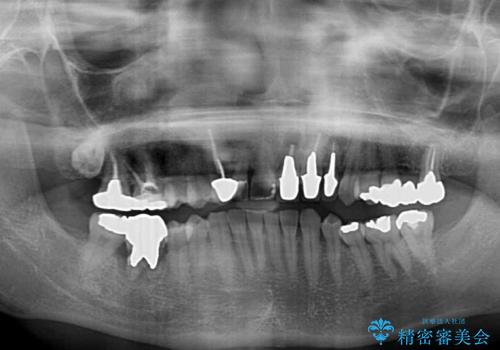

- 右下の奥歯が痛く、全体的に咬み合わせがおかしい気がするとのことで来院された患者様です。

診察したところ、上顎前歯に過剰歯があることで上顎歯列が大きくなり、上下の歯が奥歯の一部でしか咬み合っていない状態でした。

そのため右下の奥歯に強い負担が生じていて、むし歯が大きかったこともあり、抜歯が必要な状態でした。

咬み合わせ改善のため、前歯の過剰歯を抜去し、ワイヤー矯正にて歯列と咬み合わせることとしました。

左上の奥歯のブリッジや前歯のセラミッククラウンはいったん除去し、矯正治療後に補綴治療を行うこととしました。

また、右下の抜歯が必要な奥歯は、矯正治療の途中でインプラントを埋入し、矯正治療後に上顎と合わせて補綴治療を行うこととしました。